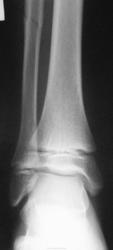

Перелом-эпифизеолиз дистального метаэпифиза ББК со смещением под углом кзади, перелом н/3 диафиза МБК

А щель перелома разве не уходит в диафиз?

Да, линия перелома распространяется и на диафиз